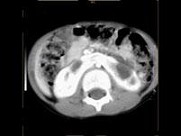

- 多项选择题女,6个月, CT扫描如图所示,下列说法正确的是 ( )

A、双侧肾盂积水

B、双侧肾门朝向前内方

C、双肾下极融合

D、考虑为异位肾

E、考虑为马蹄肾

- 女,6个月, CT扫描如图所示,下列说法